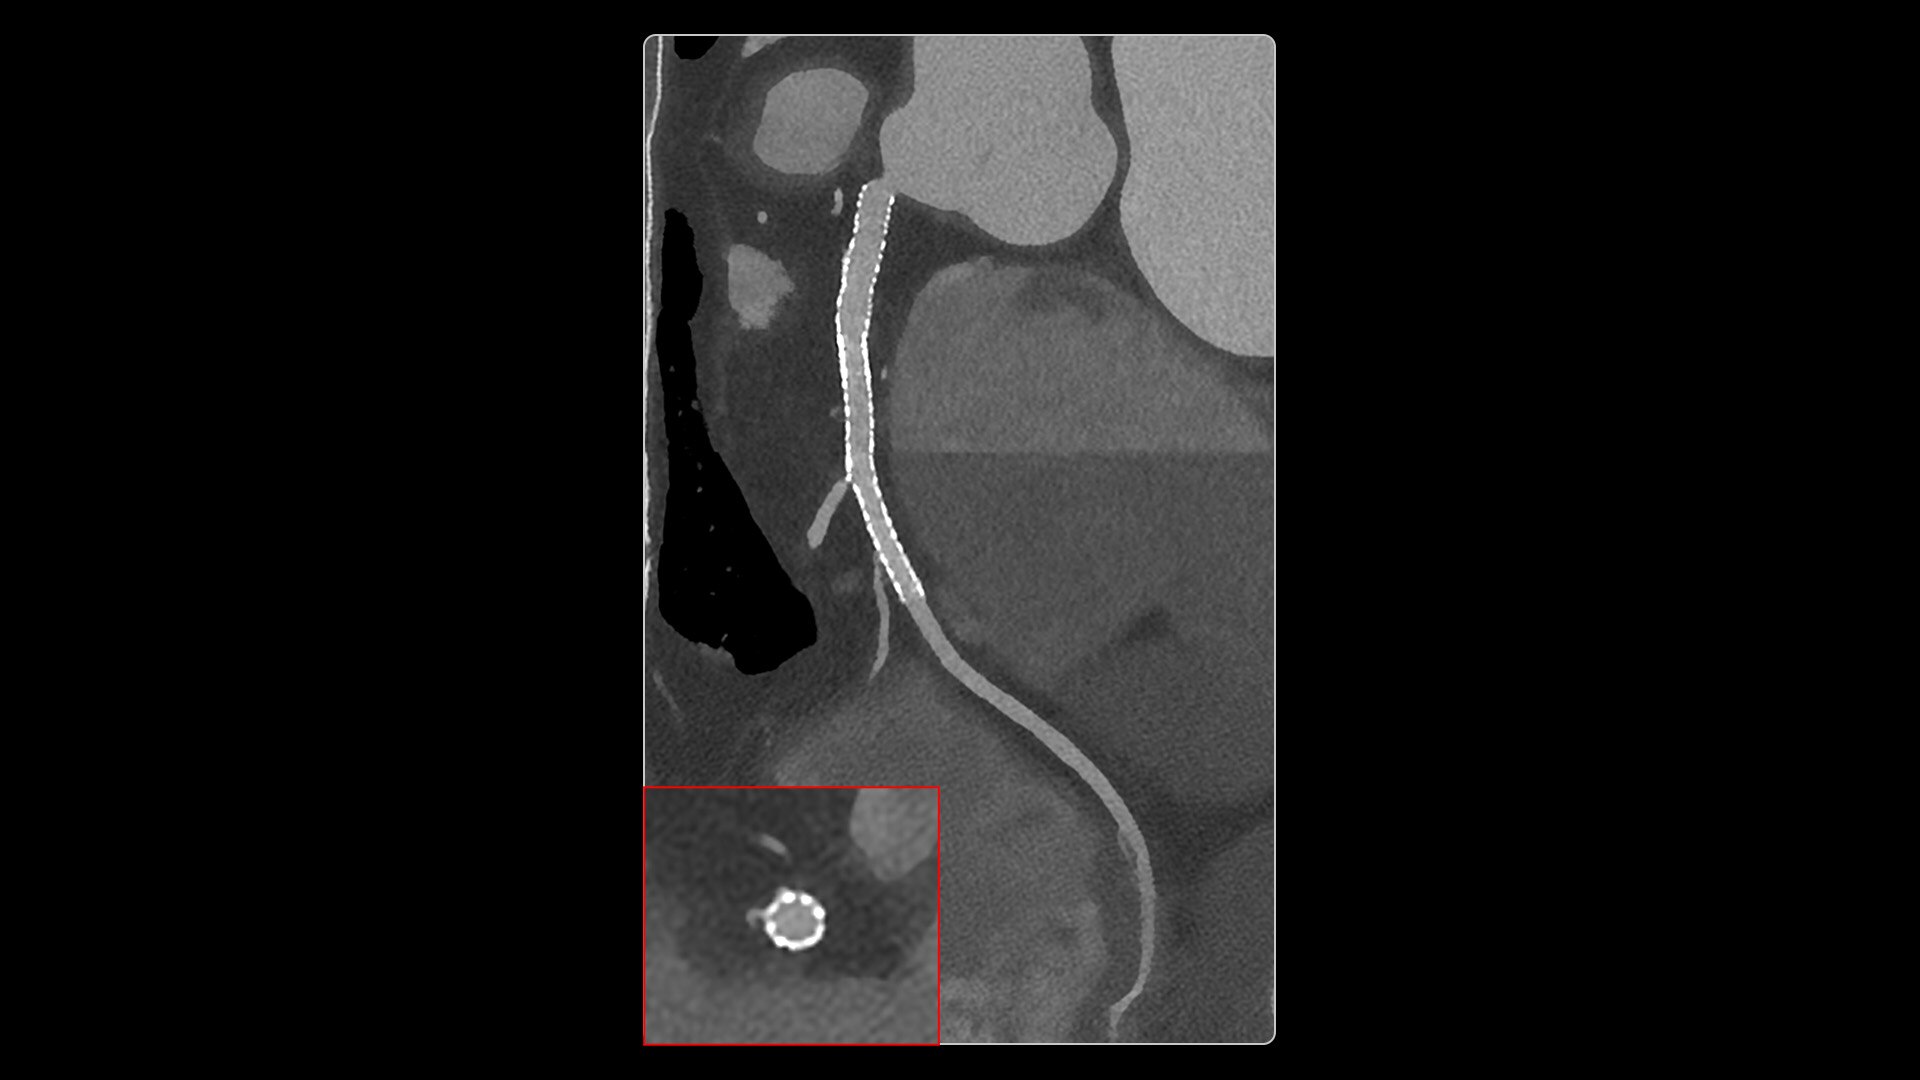

With ultra-high spatial resolution scanning capability, Photonova Spectra is designed to help you see incredibly fine details, such as coronary plaque delineation, small microvascular vessels and even tiny structures of the inner ear.

Our advanced spectral imaging capabilities are intended to allow you to experience the difference between seeing and knowing so you can confidently detect, characterize and monitor disease.

Photonova Spectra is also designed to enhance material separation for tissue characterization and disease quantification, bringing potentially greater diagnostic confidence in every acquisition across care areas.

A full range of spectral imaging series is generated natively on console and available for transfer to PACS. The full-fidelity spectral data acquisition is intended to provide native DICOM images and material maps to support clinical diagnosis, with improvements of up to 4x enhanced energy discretization1, 2x higher material map spatial resolution2, and 2x improved iodine detectability3.